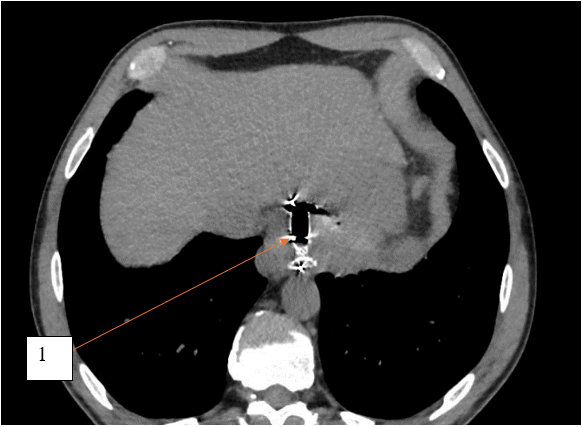

По данным компьютерной томографии органов брюшной полости с внутривенным контрастированием выявлена структура жидкостной плотности в области кардиального отдела желудка без убедительной связи с просветом желудка. Единичные увеличенные параэзофагельные, паракавальные, парааортальные лимфоузлы. Другой патологии не выявлено. Результаты компьютерной томографии с внутривенным контрастированием представлены на рисунках 1 и 2.

Рис. 2. Компьютерная томограмма с внутривенным контрастным усилением, пациент К., 54 года, аксиальный срез, отсроченная фаза. 1 – структура жидкостной плотности в области кардиального отдела желудка

Fig. 2. Computed tomogram with intravenous contrast enhancement, patient K., 54 years old, axial section, delayed phase. 1 – liquid density structure in the cardiac region of the stomach